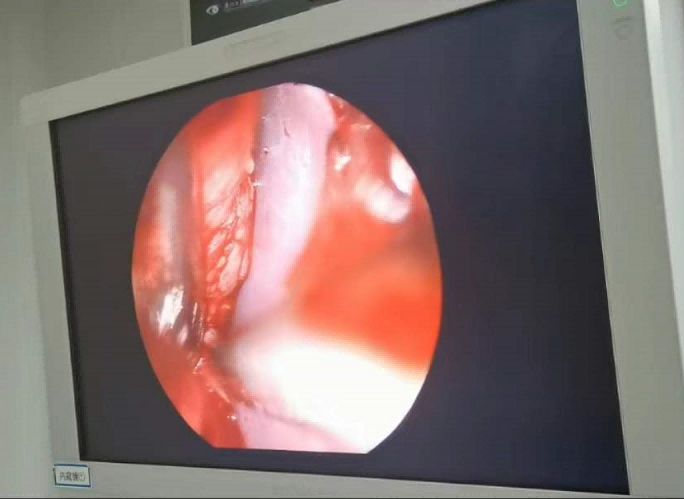

送到廈門眼科中心的時候,林老師受傷的左眼還在流血。眼整形科的鄧坤明副主任醫(yī)師緊急為他安排了“內鏡下眶骨折修補+鈦網鈦釘植入術”。

圖為:內鏡下眼眶骨折修補術

手術過程中林老師還出現(xiàn)了驚險的眼球后大出血,還好鄧坤明于緊急之中穩(wěn)住了病情,并順利完成了手術。術后第二天,林老師的術后反應就很輕,恢復良好,他一邊感謝著鄧坤明的“救命之恩”,一邊自嘲著自己示范了個“反面教材”。